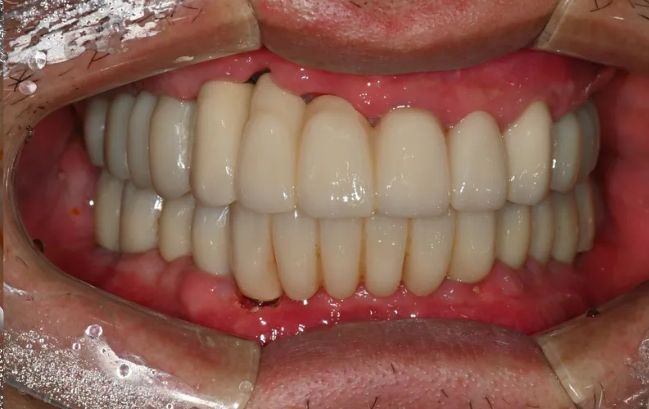

2022-03-0560대 남성, 수면 전체 임플란트 13개 식립

2021-09-06